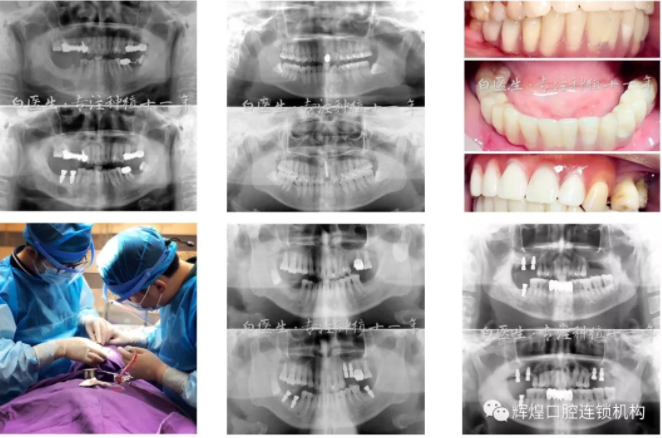

白彭院长从事口腔种植临床专业多年!

种植牙是人类的第三副牙齿,为许多患者带来了健康。